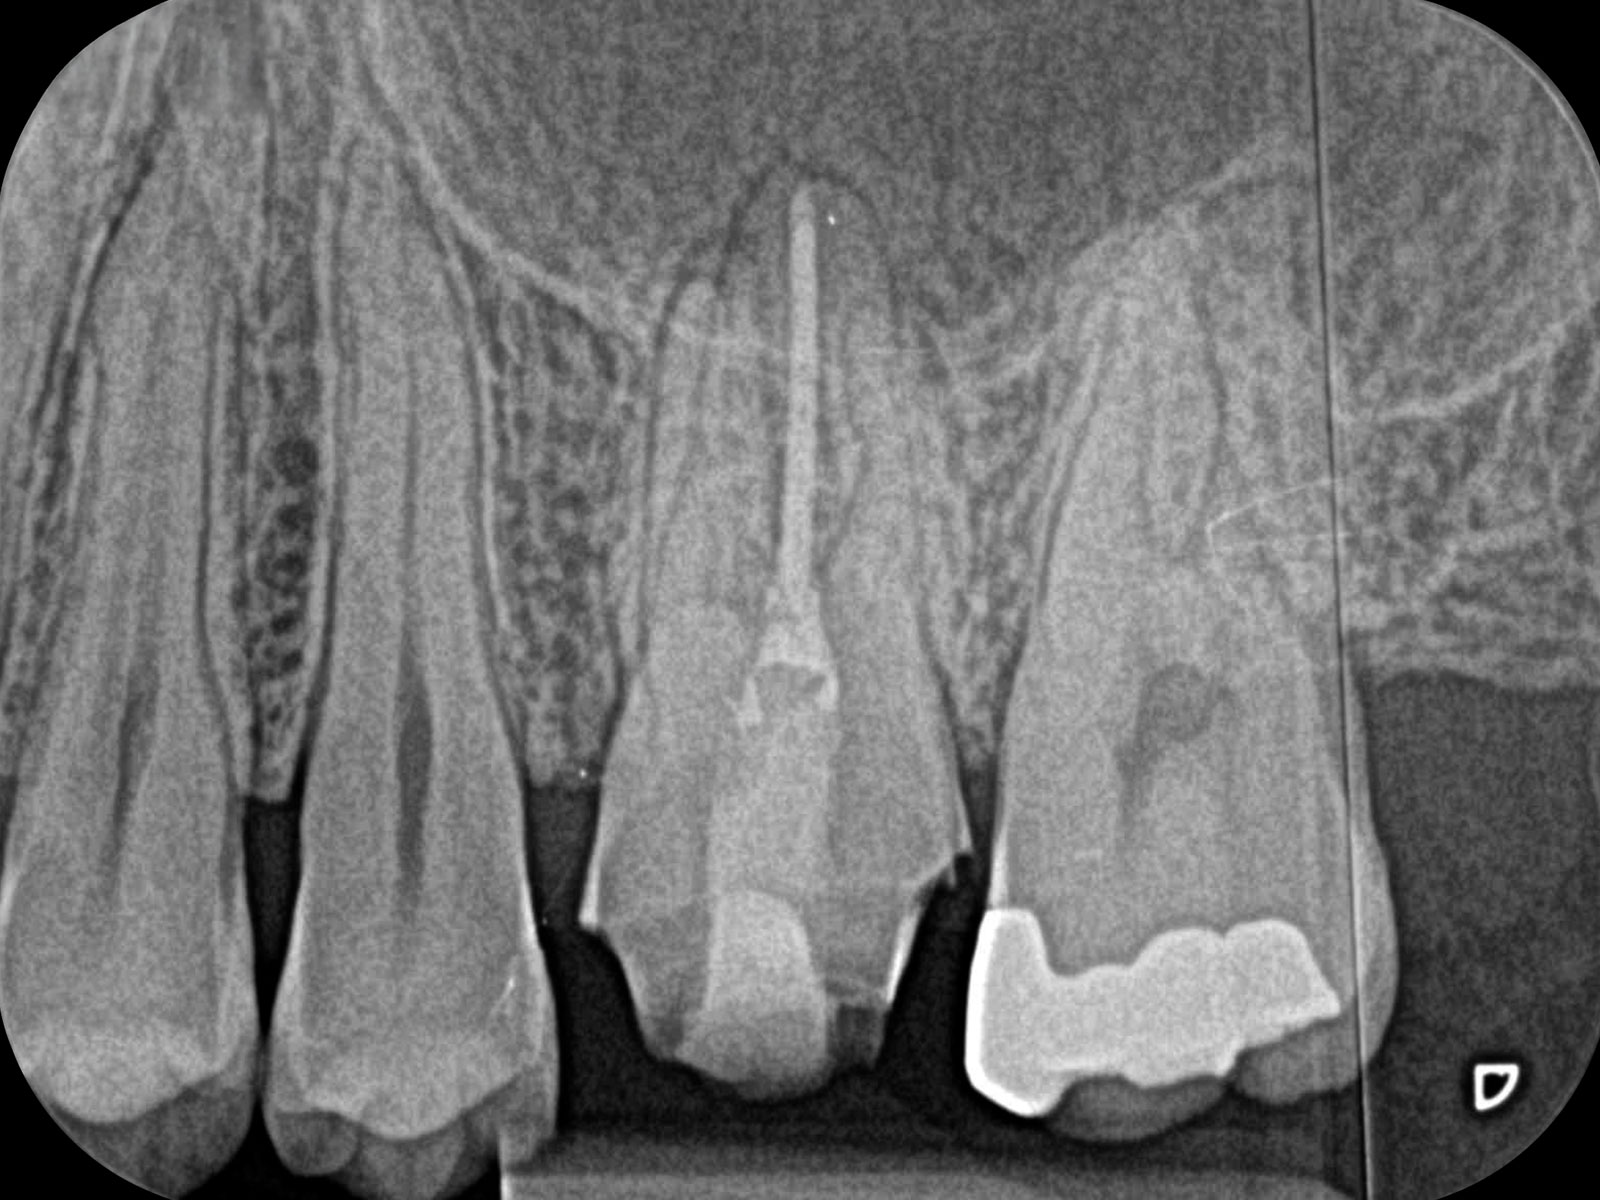

「CT」とは、X線を使って歯や骨の様子を撮影できる装置です。お口の周囲を回転しながら立体的に撮影するので、2次元で撮影するレントゲンと比べて、鮮明な画像が得られます。

画像が鮮明になることで、治療の精度も大きく変わります。次の写真は、同じ部位を「CT」(左)と「レントゲン」(右)で撮影した画像です。黒い影は問題が発生している箇所で、左の「CT画像」にはしっかり映っていますが、右の「レントゲン画像」にはありません。

レントゲンだけで撮影をしていたら、この問題は見落とされていたことでしょう。そのまま治療が行われなければ、炎症が悪化して、最終的に「抜歯」になっていたかもしれません。CTで撮影していれば、見落とされること無く、適切な治療が行えます。